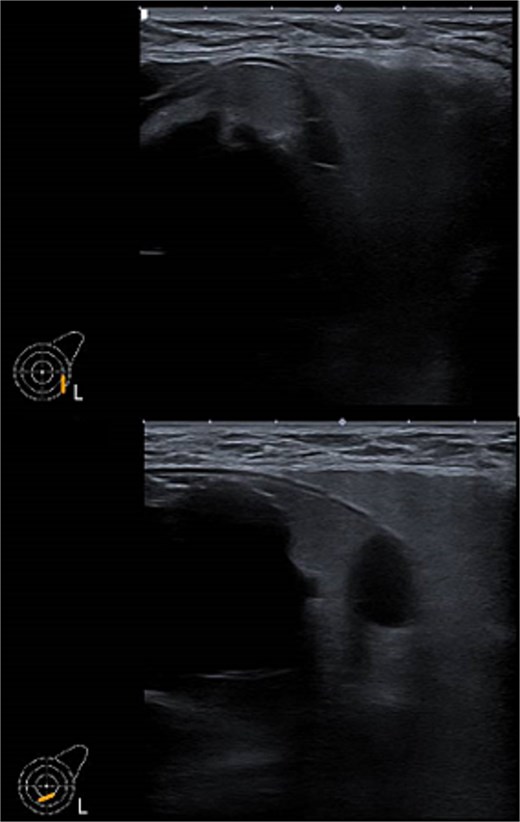

One week later, the patient reported a new lump in the left supraclavicular area. Examination revealed a 2 × 3 cm, nontender, mobile mass, confirmed by ultrasound to be silicone deposition (Figs 3 and 4). Increased breast swelling and lymphadenopathy were attributed to implant rupture and silicone migration.

Typical snowstorm appearance of supraclavicular silicone lymphadenopathy.

Imaging is a vital first step in the diagnostic evaluation of patients with lymphadenopathy. Ultrasound is the primary tool for diagnosing silicone lymphadenopathy, while additional imaging techniques, including MRI, CT, and mammography, can offer further insights for confirmation and detailed assessment of lymphadenopathy [11]. The sensitivity and specificity of using ultrasound to diagnose silicone lymphadenopathy by identifying the snowstorm sign have been reported as 87.5% and 100%, respectively [11]. In our case, the ultrasound typical snowstorm appearance was enough to make the diagnosis. Even though if any clinical concern about malignant or infectious process, cytological or histological evaluation is mandatory to confirm the diagnosis. Also in patients with previously treated breast cancer and having the implant as reconstructive measure; concerns about disease recurrence should be carefully considered.